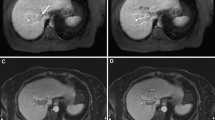

Image processing was performed in Vitrea Advanced Visualization software (Vital Images, Minnetonka, USA) to evaluate the size and shape of each ablation. Ablation size was measured in millilitres (mL) and derived from the images using a semi-automated segmentation tool with adaptive thresholding. The ablation diameter was recorded in three axes, as shown in Figure 2: a long-axis diameter (LAD) in plane with the needle insertion axis and two orthogonal short-axis diameters (SAD). The sphericity index (SI) was defined as the ratio between those diameters \(\frac{{\mathrm{SAD}}_{1}+{\mathrm{SAD}}_{2}}{2\mathrm{LAD}}\). An SI of 1 therefore denotes a perfectly spherical ablation, whereas a lower SI means that the ablation shape is more elliptical. Imaging parameters were acquired blinded from system and settings.

An example of the post-ablation liver MRI can be found in Figure 3. Table 1 shows the median ablation volume for the 48 ablations. Amica ablations were significantly larger than Emprint ablation (p < 0.001), with a median ablation volume of 21.1 mL versus 11.1 mL. Figure 4 shows all individual ablation volumes per setting. For all settings, the range of ablation volumes was smaller for Emprint ablations compared to ablations produced with the Amica system (Table 1 and Figure 4).